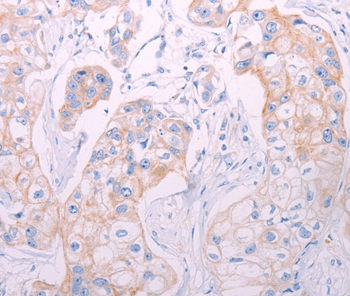

Immunohistochemical analysis of paraffin-embedded Human breast cancer tissue using #37313 at dilution 1/50.

应用详情:Immunohistochemistry: 1:25-1:100